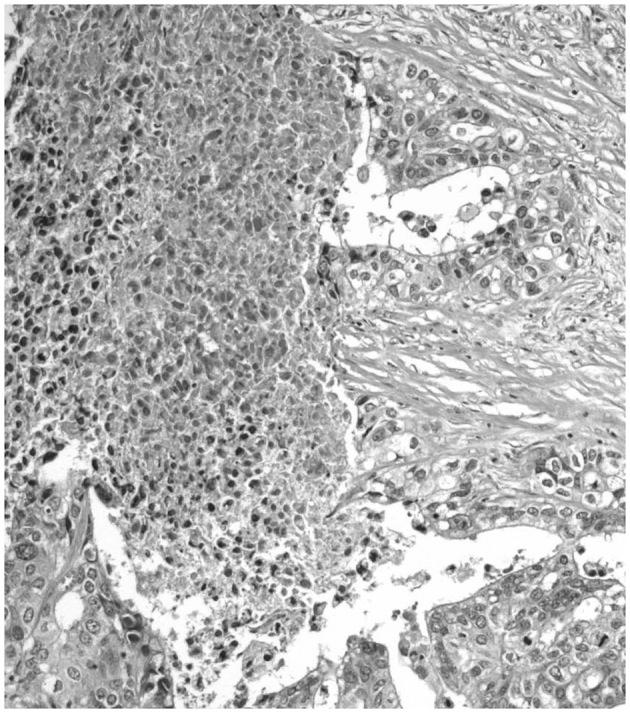

Histological tumor necrosis (TN) has been reported to indicate a poor prognosis for different human cancers. It is generally accepted that TN results from chronic ischemic injury due to rapid tumor growth. However, whether insufficient tumor vascularization and inadequate tumor cell oxygenation are the only factors causing TN remains controversial. Mitotic catastrophe is considered to occur as a result of dysregulated/failed mitosis, leading to cell death. We hypothesize that mitotic catastrophe, induced by hypoxic stress, may lead to the TN which is observed in high grade carcinomas. The current review describes the morphological features of TN in malignant epithelial tumors. In addition, evidence regarding the involvement of mitotic catastrophe in the induction of TN in human carcinomas is discussed.

据报道,组织学肿瘤坏死(TN)提示不同人类癌症的预后不良。人们普遍认为,TN是由肿瘤快速生长导致的慢性缺血性损伤引起的。然而,肿瘤血管生成不足和肿瘤细胞氧合不足是否是导致TN的唯一因素仍存在争议。有丝分裂灾难被认为是由于有丝分裂失调/失败导致细胞死亡而发生的。我们假设,由缺氧应激诱导的有丝分裂灾难可能导致在高级别癌中观察到的TN。本综述描述了恶性上皮肿瘤中TN的形态学特征。此外,还讨论了有关有丝分裂灾难参与人类癌症中TN诱导的证据。